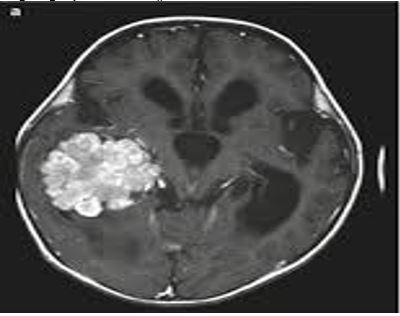

Enhanced Brain Tumor Diagnosis with EfficientNetB6: Leveraging Transfer Learning and Edge Detection Techniques

Adnan Hameed, Arsalan Khan, Sohail Ahmad, Sibghat Ullah, Abdul Nasir Khan, Sadiq Nawaz Khan

796-807